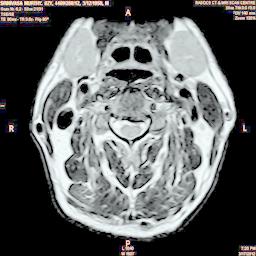

The developed algorithm presented in the previous section was coded using Matlab Version 8.0. The experiment was conducted by considering poor quality spinal cord images of having various lesions. The first column of Fig. 4 shows the axial view of neck spinal cord images of size pixels, respectively. The second column of Fig. 4 presents the same images enhanced using histogram equalization. As is evident from the results presented, the histogram equalization method performs global image enhancement operation which improves the contrast of an image but at the cost loss in image details. The third column of Fig. 4 shows the MSR based spinal cord image enhancement. It can be seen that from the result presented, MSR scheme improves the details that are not clearly visible in histogram equalization technique. In general, image enhancement achieved by MSR method is better compared to histogram equalization. However, the MSR method voilates gray world assumption. Therefore, the image enhanced by this scheme appears to be grayish. Although, numerous work have been reported for solving the problem due to gray world voilation, no work seems to developed for complete elimination.

The fourth column of Fig. 4 shows the image enhanced using Chao et al. []. It can be seen from the results presented that the reconstructed images of Chao’s method have black spots. The appearance of these dark patches degrades the visual quality of the enhanced image. The image enhanced using proposed multirate multiscale retinex image enhancement method presented in the fifth column of Fig. 4, overcomes the drawback of the Chao’s method. As we can see from the simulation results, image enhancement achieved by the proposed method has improved details with significant contrast enhancement. The enhanced images from the proposed method provides information to physicians, radiologists and researchers for various types of pathology detection.